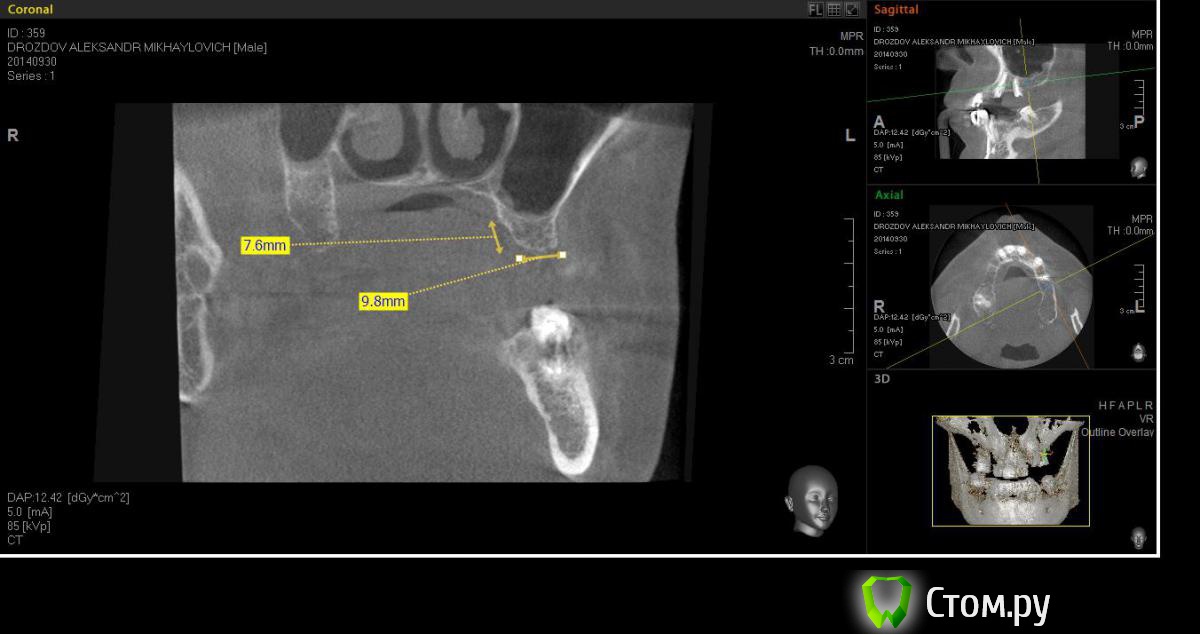

Neilrus Опубликовано 5 октября, 2014 Поделиться Опубликовано 5 октября, 2014 (изменено) Здравствуйте. Помогите добрым советом отностительно имплантата 26з , высота примерно 7,5 до пазухи, ширина впечатляет, почти 9,5.Планируем имплантацию вч. С первым квадрантом все ясно, синус на два дистальных имплантата с латеральным доступом. Ставим систему Xive. Второй квадрант, хочу попробовать систему AnyRidge, они есть очень широкие за счет лопастей резьбы с узким телом, площадь обещают на 50 % больше чем у аналога такой же высоты и диаметра, не хочется ему второй синус без необходимости делать. ВОПРОС: Поставить во второй квадрант Xive широченный и короткий с поднятием крыши пахухи крестально на 0,5-1 мм 5,5*8 чтобы с обеих сторон была одинаковая система?Либо поставить AnyRidge высотой 6,5*7 без вмешательства в пазуху ? но тогда разная система с двух сторон, ни разу так не протезировал, это будет проблемой? Как вы считаете? Прикалываю фото кт 26 зуба, и заодно первый квадрант для интереса.Спасибо. Изменено 5 октября, 2014 пользователем Neilrus Ссылка на комментарий